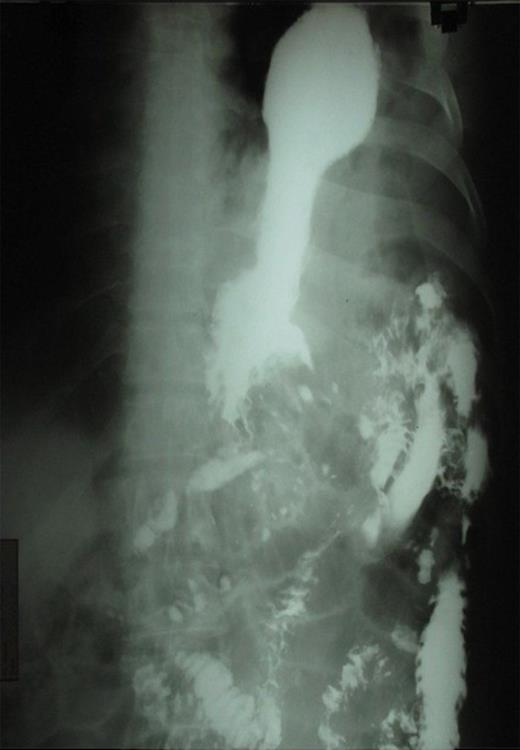

The patient was counseled and prepared for surgery through a left sub costal incision. The findings at surgery were that two-thirds of the stomach, omentum and spleen had herniated through a 10cm X 7cm tear in left hemidiaphragm into the chest. (Figure 3) Contents were normal and reduced into the abdomen. An intercostal chest tube drain was guided in the left thoracic cavity. Diaphragmatic tear was repaired with horizontal mattress prolene suture. Postoperative period was uneventful. Follow-up after 1 year showed no recurrence.